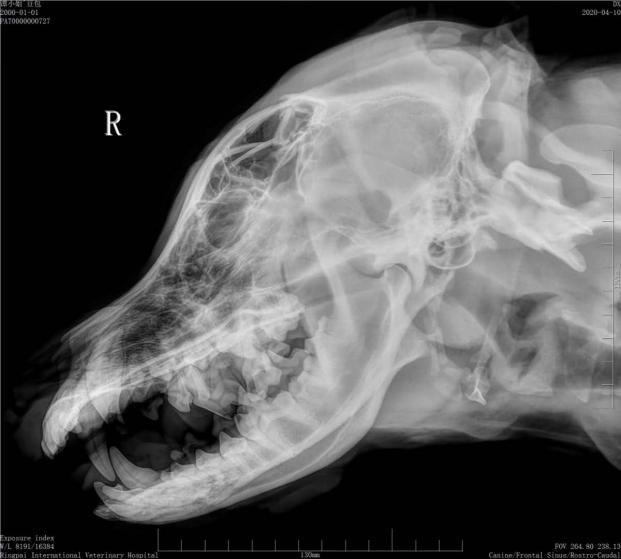

术前影像